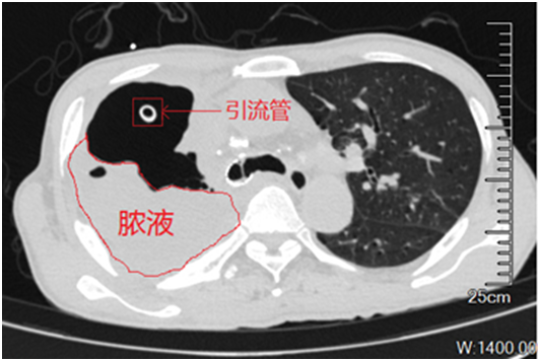

脓胸最常见的致病菌是铜绿假单胞菌。在可以用来治疗该细菌的药物中,碳青霉烯类抗生素是抗菌谱最广、抗菌活性最强的药物。不幸的是,该患者脓胸分泌物培养出来的铜绿假单胞菌,不仅对常用的抗生素耐药,而且对碳青霉烯类也耐药。在近2个月的各种抗生素治疗后,患者的脓胸没有得到控制:支气管胸膜瘘还一直往外漏气漏液,右边胸腔一半都是脓液,引流脓液的管子还在咕噜咕噜的冒着气体。卢洪洲教授团队经过会诊,仔细评估,决定给患者进行噬菌体治疗。噬菌体是一种以细菌作为宿主的病毒,显微镜下它有一个菱形的脑袋、长长的脖子,还有六个爪子,像个机器人一样。它会先吸附在细菌表面,然后把自己的DNA注入细菌体内,DNA在细菌体内大量复制使细菌裂解,从而杀灭细菌。随着细菌耐药问题日趋严峻,噬菌体疗法成为耐药细菌治疗的一种潜在的补充或替代疗法。